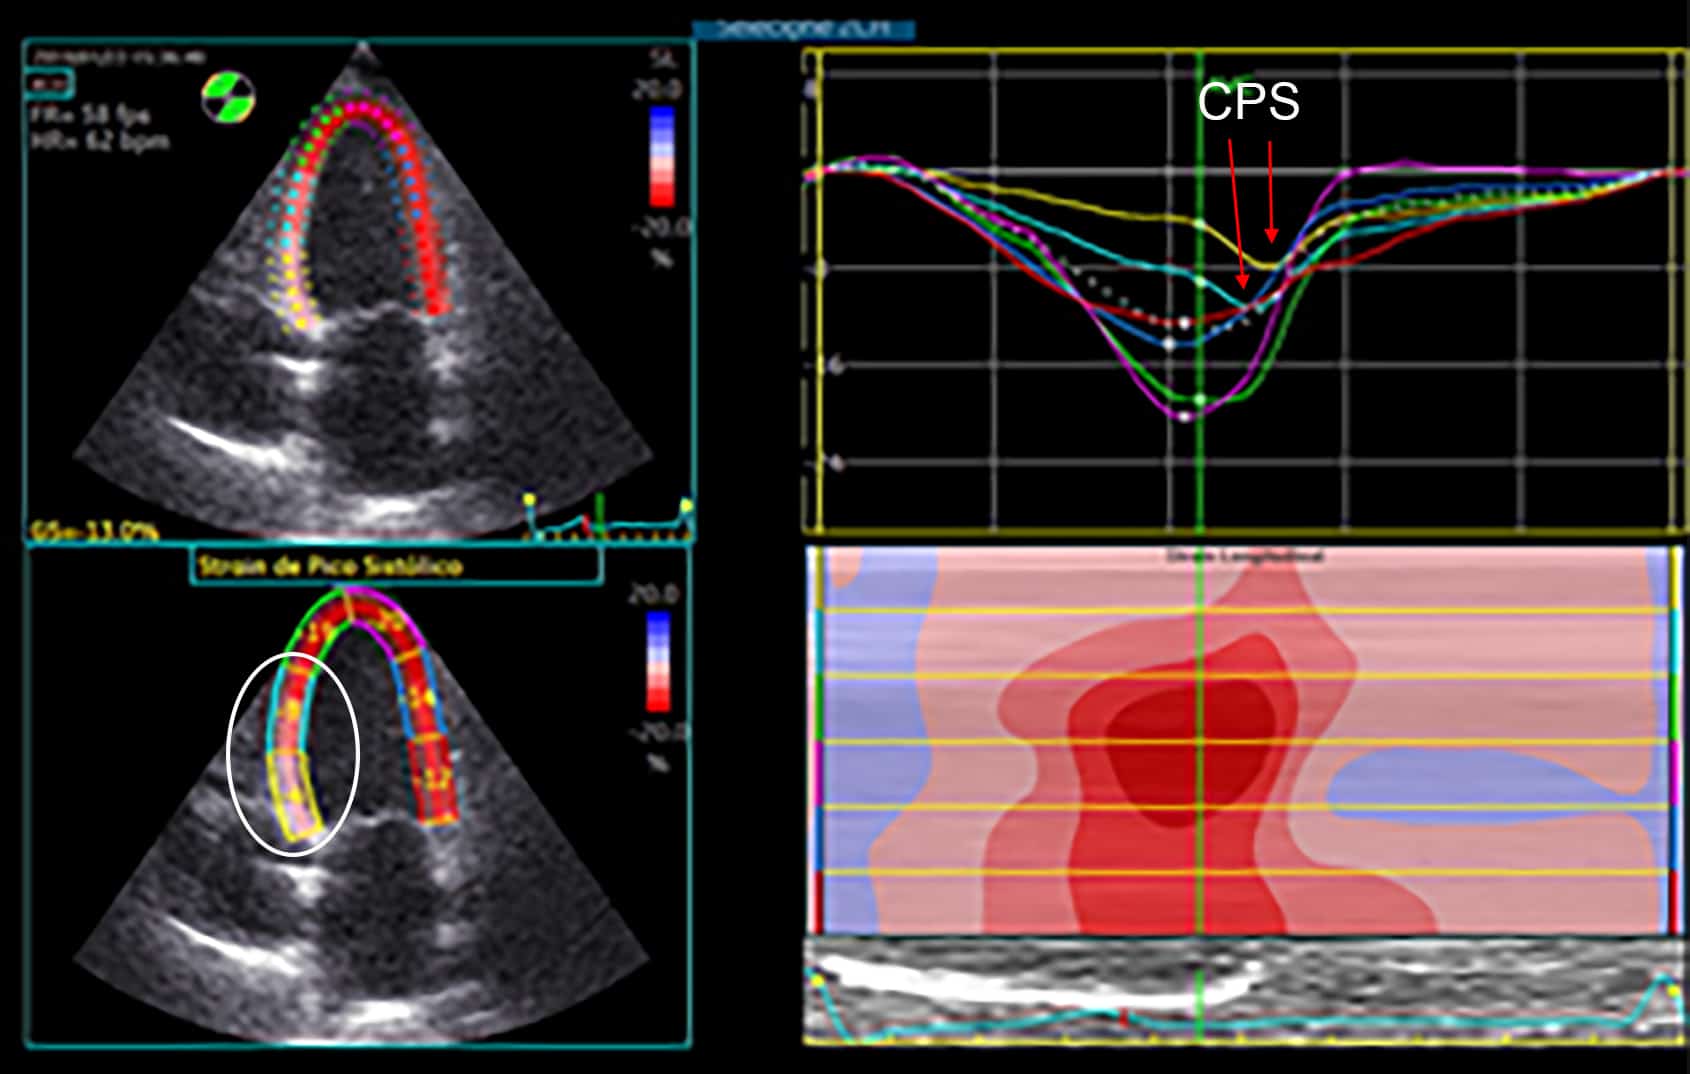

ECOCARDIOGRAFIA DE ESTRESSE PARTE 3 Blog Ecope Tapse Ecocardiografia Aunque únicamente evalúa la contracción longitudinal del vd, ha demostrado una buena correlación con otras medidas que evalúan la función sistólica global. Rv 2d fac 19 8.4. 141 rows el desplazamiento sistólico del plano del anillo tricuspídeo (siglas en inglés, tapse) es una medida ecocardiográfica que. tricuspid annular plane systolic excursion (tapse) is an echocardiographic measure that allows. Tapse Ecocardiografia.

La valutazione ecocardiografica della funzione ventricolare destra Tapse Ecocardiografia the ratio of tricuspid annular plane systolic excursion/systolic pulmonary artery pressure (tapse/pasp, measured by echocardiography) has been. Rvot, pulmonary valve, and pa 41 b. tricuspid annular plane systolic excursion (tapse) is an echocardiographic measure that allows us to assess right ventricular systolic. Aunque únicamente evalúa la contracción longitudinal del vd, ha demostrado una buena correlación con otras medidas. Tapse Ecocardiografia.